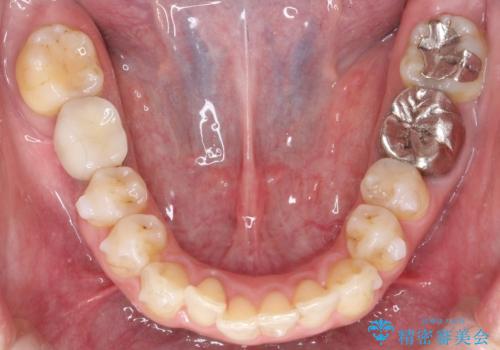

- 前歯のがたつきを主訴に来院されました。

なるべく目立たない矯正をご希望されたので、インビザラインにて治療することとなりました。